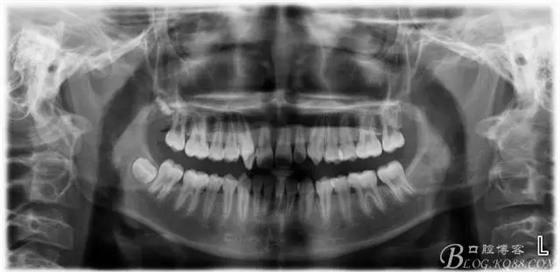

患者13歲,男性,自覺牙齒不齊要求矯正;

通常情況下,前牙反合的患者因上頜發(fā)育不足,會(huì)伴發(fā)上頜前牙區(qū)牙列擁擠;

矯正過程中對(duì)牙周進(jìn)行了手術(shù)治療;